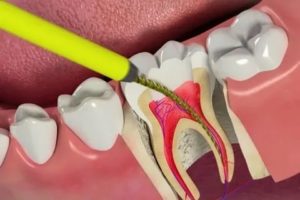

Лечение и чистка каналов зуба выполняются следующим образом:

- Проводится анестезия участка, на котором расположен больной зуб.

- Врач удаляет инфицированные ткани зубной коронки, формирует полость, вскрывает пульповую камеру.

- Проводится удаление пульпы витальным или девитальным методами – конкретный способ выбирается в зависимости от вида зуба и степени воспалительного процесса.

- Выполняется тщательная чистка корневых каналов от остатков пульпы и инфицированных тканей.

- Проводится антисептическая обработка стенок канала, а также медикаментозная обработка для лучшей адгезии пломбировочного материала.

- Врач пломбирует каналы, затем пломбирует коронковую часть зуба, полностью восстанавливая ее целостность.